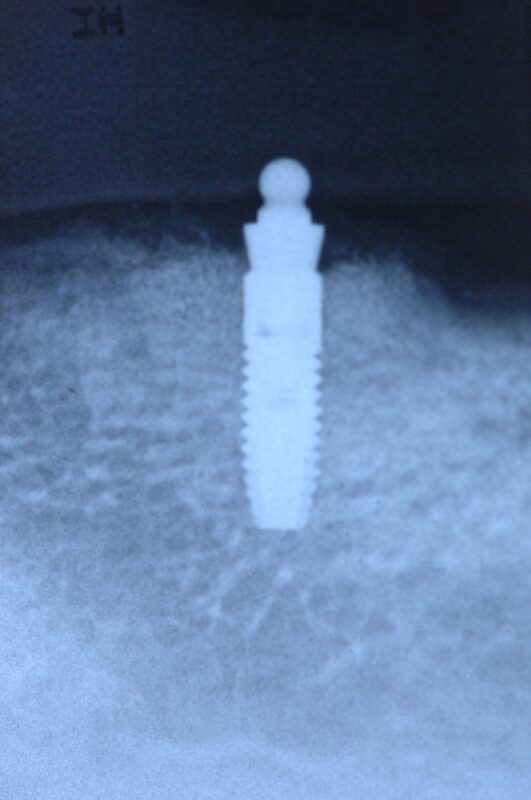

ミニダルロという義歯+インプラント治療方法

総義歯安定のため、インプラント2本埋入し、その上部にミニダルロというアタッチメントを装着し、

総義歯を安定させます。